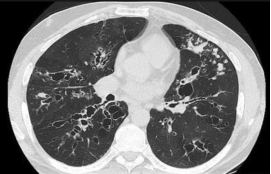

1. 高分辨率CT(HRCT):这是诊断支气管扩张的“金标准”。它可以清晰地显示出支气管是否扩张、增厚,形态是“柱状”、“囊状”还是“静脉曲张状”,就像给肺部做了一个精细的三维扫描。